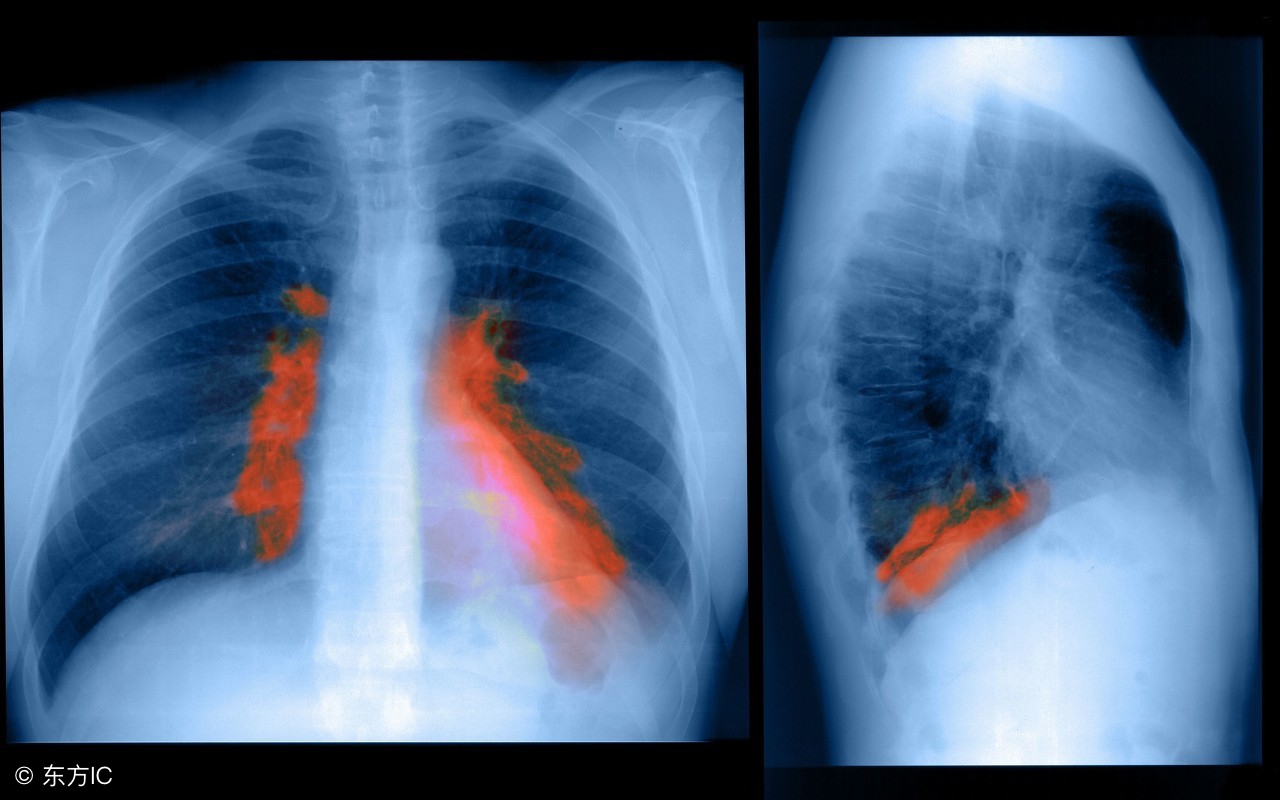

有些患者在临床上进行肺部检查的时候,结果可能会提示:肺内存在有条索状斑片状影的情况,此时患者们往往会担心,这种条索状、斑片状影会是恶性肿瘤存在的提示吗?什么情况下需要警惕存在恶性可能,需要治疗?

1、什么是“肺部见条索状斑片状高密度灶”?

这是检查术语,“肺部见条索状斑片状高密度灶”通俗来讲就是肺部有渗出性的病理变化,之所以会出现这一情况,可能是机体以往患有肺结核、肺炎、肺脓肿、肺囊肿、肺动脉瘤、肺出血等肺部疾病遗留的陈旧性病灶导致的,其中以肺部炎块多见。在临床上,绝大部分患者的疾病都是良性的,如若没有任何症状或是不舒服的表现,此时一般不需要进行特殊的治疗,可以定期复查胸部ct检查看看即可。